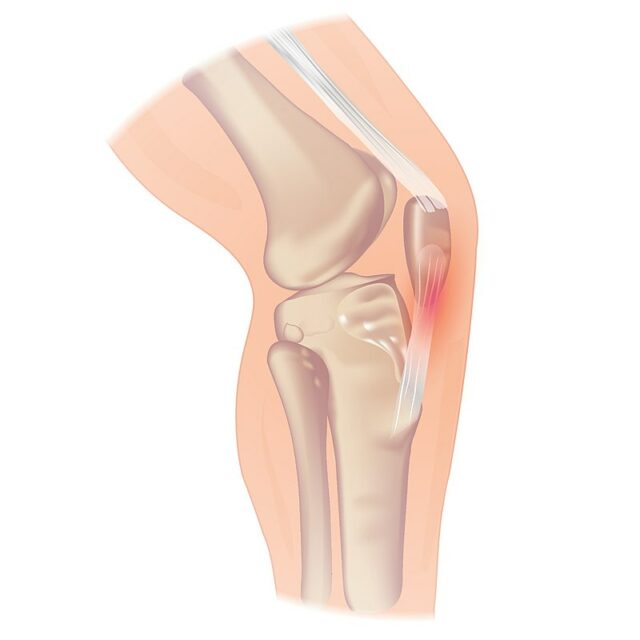

Хотя тендинопатия надколенника может возникнуть в нижнем полюсе надколенника, она также может возникнуть в месте впадения сухожилия в бугорок большеберцовой кости, что встречается реже. Если пациент сообщает о боли у основания коленной чашечки, ты можешь заподозрить тендинопатию квадрицепса.